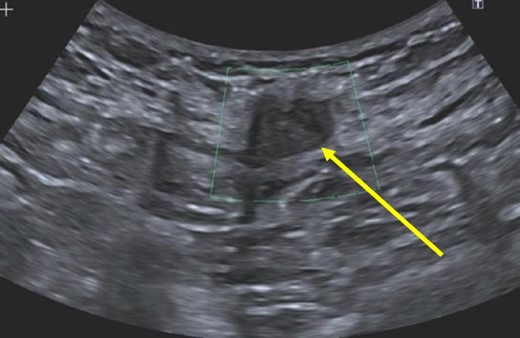

A 38-year-old female with past medical history of hypertension, migraine headaches, and anemia as well as past surgical history of two Cesarean sections presented to our general surgery clinic with a painful abdominal mass at the left lateral aspect of her Pfannenstiel incision. She reported that her most recent Cesarean section was 4 years ago with recurrent pain over the incision for about 2 years. Of note, 2 years prior to presentation at our clinic, she was seen by a general surgeon for similar symptoms and was found to have two subcutaneous nodules at the lateral edge of the Pfannenstiel scar. Ultrasound of the region at that time showed two hypoechoic, nonvascular, and non-fluid-filled subcutaneous nodules suggestive of suture granulomas (Fig. 1). Since then, she had experienced intermittent discomfort. More recently, each month at the time of menstruation, she stated that the mass would enlarge and become more painful. After menstruation, the mass would decrease in size and the pain would recede. On this visit, ultrasound revealed a heterogeneous vascular soft tissue mass measuring 4.1 × 3.3 × 4.4 cm, suspicious for endometrioma in the setting of her clinical history (Fig. 2).

Hypoechoic, nonvascular, non-fluid-filled subcutaneous nodule (arrow), likely suture granuloma.